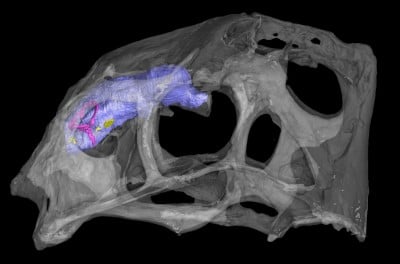

Newswise — On this World Anatomy Day, Oct. 15, experts in the Center for Functional Anatomy and Evolution at Johns Hopkins Medicine are working to find answers to evolutionary mysteries. Using…

Newswise — On this World Anatomy Day, Oct. 15, experts in the Center for Functional Anatomy and Evolution at Johns Hopkins Medicine are working to find answers to evolutionary mysteries. Using…